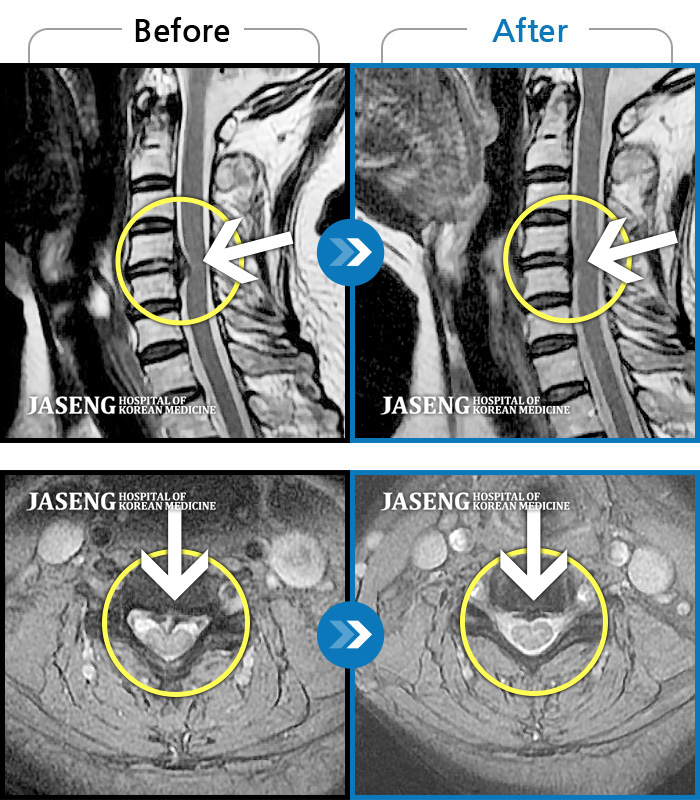

박정우 원장님 덕분에 목디스크가 많이 호전되었어요. 하지만 그 이유만으로 칭찬하는건 아닙니다. 세심한 치료와 좋은 실력,환자에 대한 배려가 조화를 이루는 참 좋은 의료인입니다.